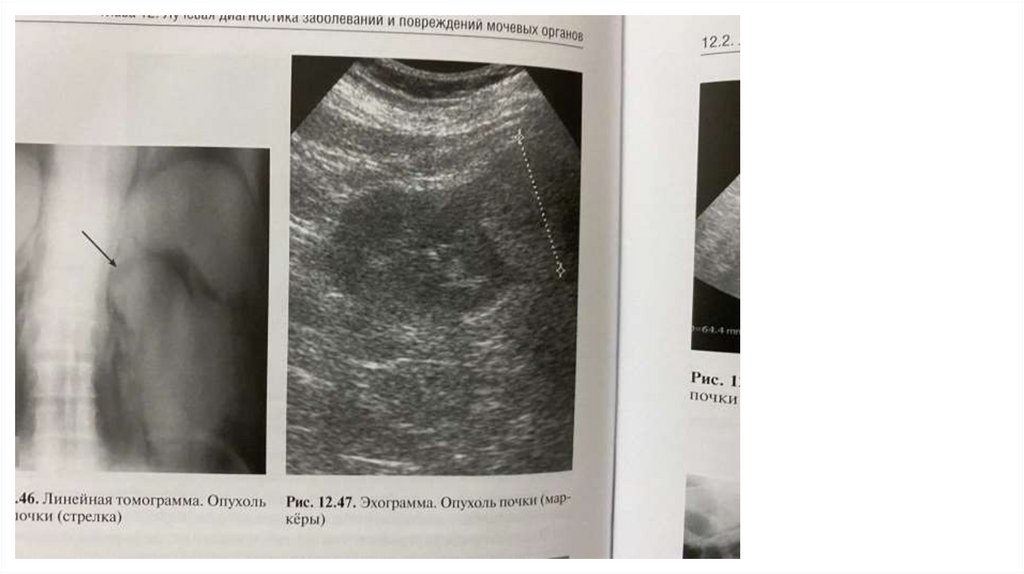

Эхоструктура злокачественных опухолей гетерогенная, с зонами всего

спектра эхогенности: анэхогенные (кровоизлияния), гипоэхогенные (некроз),

эхопозитивные (опухолевая ткань), гиперэхогенные (обызвествления).